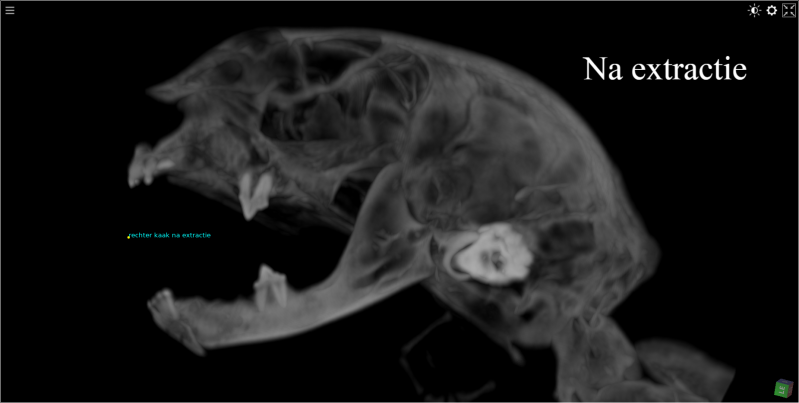

Tandverzorging bij de kat : opsporen van  aangetaste wortels en controle na verzorging